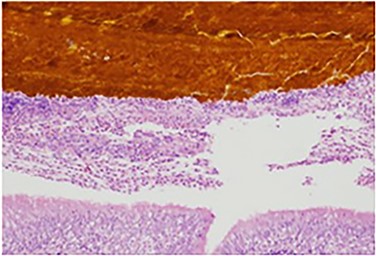

The patient recovered well, but <1 month later he noticed an additional draining sinus at the right flank. A fistulogram (Fig. 1) was performed, and it showed a connection between the sinus and a right lower lobe bronchiole. He was taken to the OR for a right thoracotomy with wedge resection of the right lower lobe of the lung and excision of a broncho-pleuro-cutaneous fistula that was found to contain pieces of golden pigmented solid material, which was concluded to be consistent with a gallstone (Fig. 2). This case report presents a patient with an uncommon complication from a dropped gallstone: a broncho-pleuro-cutaneous fistula.

Contrast study of the broncho-pleuro-cutaneous fistula formed by the dropped gallstone